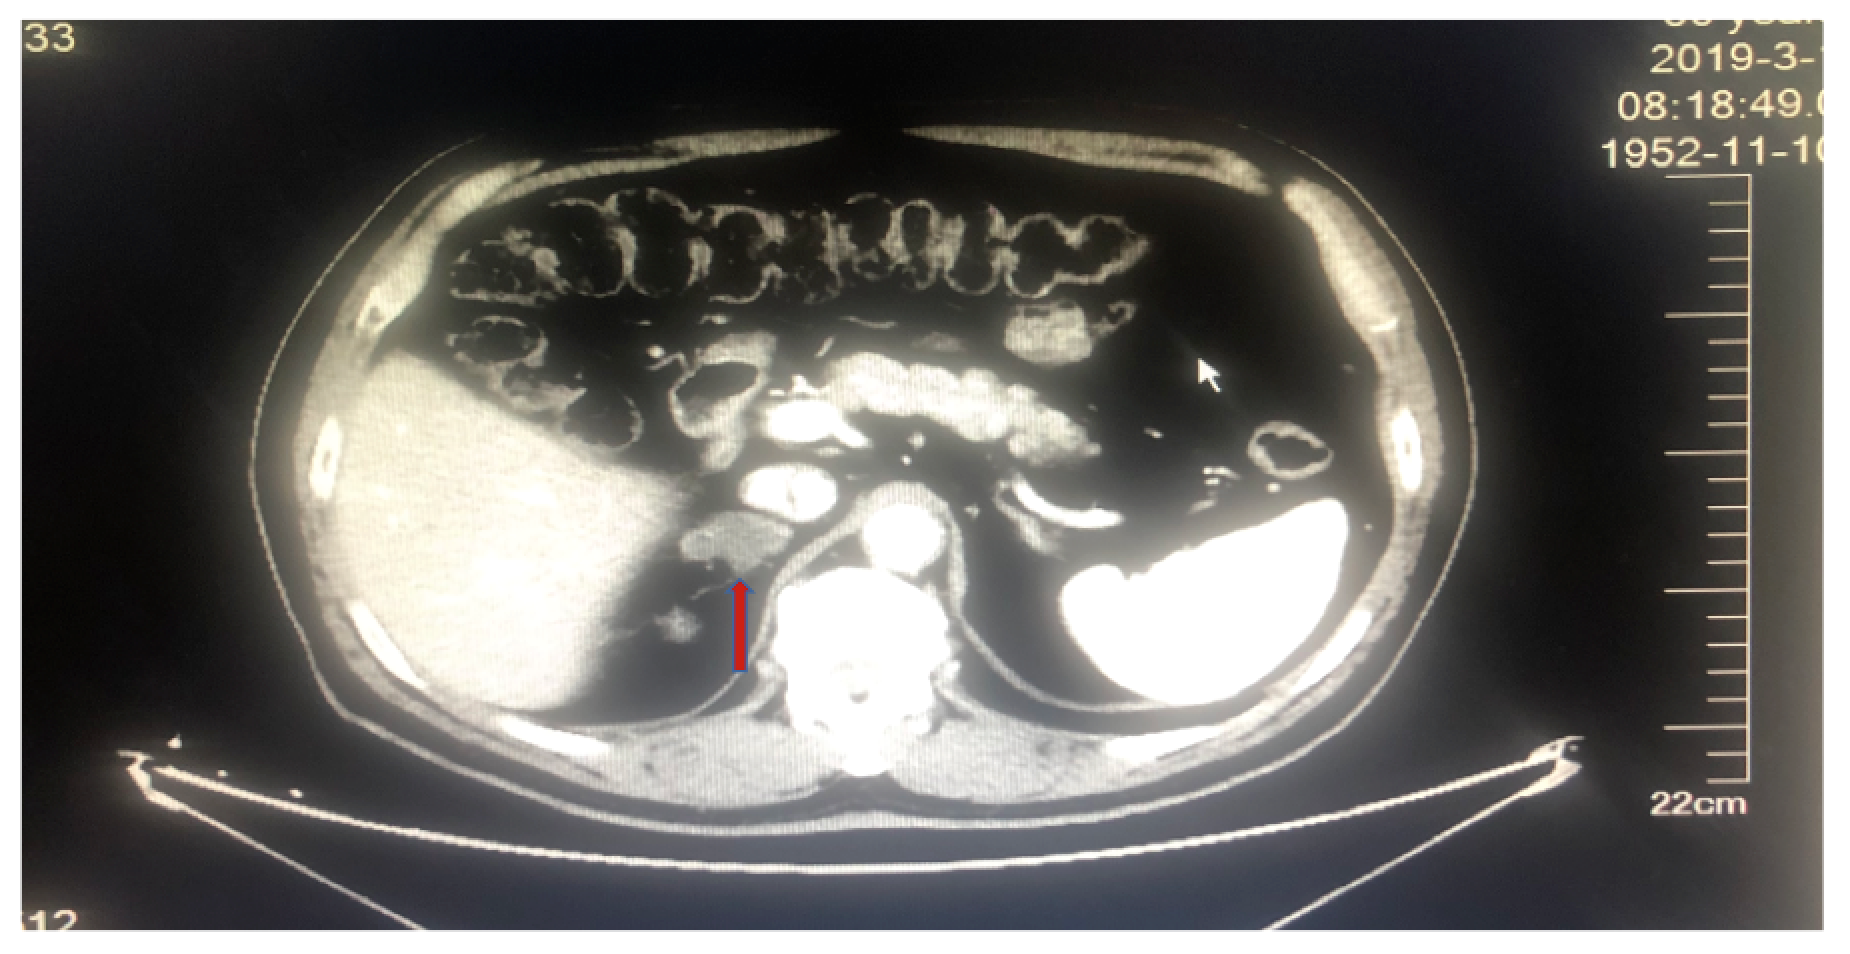

男性,66岁,吸烟30余年。因“咳嗽,咳痰带血1月”入院。既往合并糖尿病史8年,否认肿瘤家族史和其他家族性遗传性疾病史。入院行血常规、生化检查未见明显异常。肿瘤指标示NSE 23.56ng/ml、CA153 34.90U/ml。哈尔滨胸科医院胸部CT示:右肺上叶空洞伴占位性病变;腹部CT检查发现肾上腺结节。支气管镜检查病理示:“鳞状细胞癌”。诊断为:右肺鳞癌,伴纵隔淋巴结转移,右肾上腺转移;糖尿病。

图1. 基线胸部CT检查

图2. 基线腹部CT发现肾上腺转移